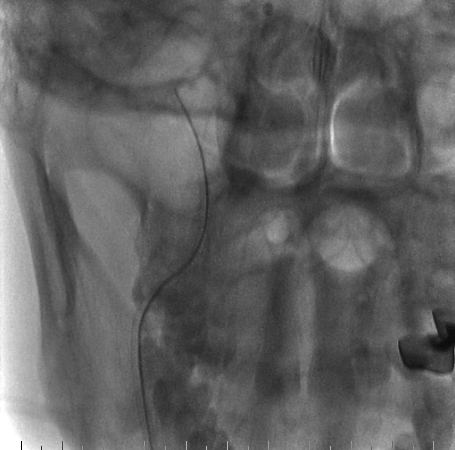

右侧桡动脉穿刺置入6F 泰尔茂薄壁鞘,Cat5中间导管同轴rebar27导管头端塑形在0.014微导丝引导下引至右侧颈内动脉海绵窦段,Cat5中间导管引入V18导丝加强系统支撑。

什么达医畅疗·第二期 | 畅医达(Choydar)17小系统血流导向装置经桡治疗大脑中动脉动脉瘤_https://www.jmylbn.com_新闻资讯_第17张